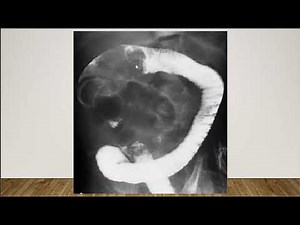

- Intussusception

Ppt Download - Air Enema

Intussusception - Rediction of

in Intussusception - Crescent Sign of